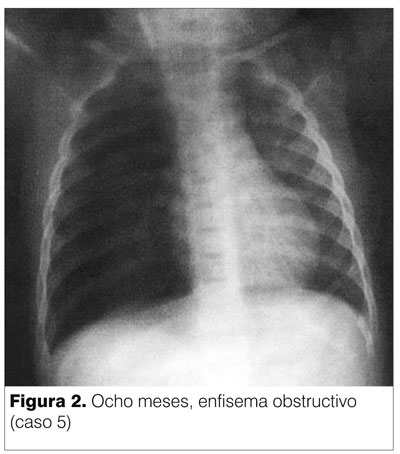

El hallazgo más frecuente es el atrapamiento aéreo o enfisema obstructivo del pulmón o lóbulo afectado cuya expresión es mayor tamaño e hiperlucidez del sector distal a la obstrucción (figura 4).

En ocasiones, para poder documentar el atrapamiento aéreo se recurre a estudios obtenidos en decúbito lateral, en inspiración/espiración o a la fluoroscopía(9).

En casos en que no se reconoce tempranamente la aspiración del CE, el enfisema es sustituido por atelectasia.

La atelectasia es más frecuente en la evolución, aunque puede ocurrir en forma rápida cuando el CE ocluye por completo el bronquio (figura 3).